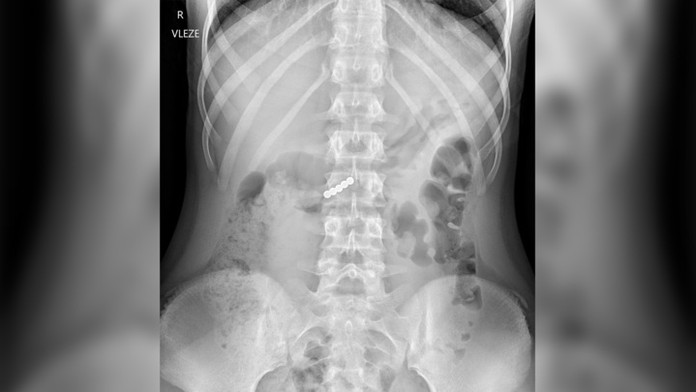

Röntgenová snímka zobrazujúca malé magnety v tele pacienta Zdroj: Facebook/Fakultní nemocnice v Motole

Deti z Česka sa zapojili do výzvy na sociálnej sieti, ktorá sa skončila hospitalizáciou v nemocnici. Päť pacientov omylom prehltlo malé magnety a čakala ich akútna operácia.

Podľa zverejnených röntgenových snímok niektoré deti omylom prehltli až päť guľôčok. Jedna pacientka mala šťastie a drobné guličky vyšli z jej tela bez problémov, no ostatní zostávajú hospitalizovaní.